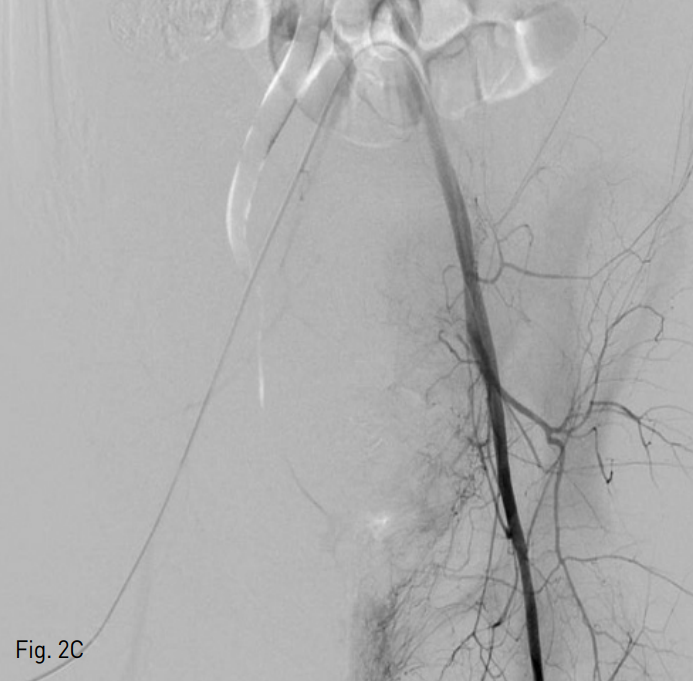

우측 총대퇴동맥을 천자한 후, 5 Fr sheath (Terumo, Tokyo, Japan)를 거치 시켰다. 이후 0.035 inch guide wire (Terumo, Tokyo, Japan)} 5 Fr pigtail catheter (Cook,Bloomington, IN,USA)를 이용하여 골반 동맥 조영술을 시행하였으며, 좌측 내장골동맥 분지에서 기시하는 분지에서 발생하고 있는 조영제의 유출 (Fig. 2A)을 확인하였다. 이어 5 Fr Cobra catheter (Cook, Bloomington, IN,USA)를 이용하여 좌측 내장골동맥을 선택한 후 시행한 조영술에서 동일 부위에 좌측 상방광동맥에서 기인한 조영제의 유출을 확인하였다. 2.2 Fr microcatheter (Progreat; Terumo, Tokyo, Japan)를 통해 좌측 상방광동맥을 초선택한 후 histoacryl glue (B. Braun, Melsungen AG, Germany)와 리피오돌 1 : 3 혼합액 1 cc를 이용하여 색전술을 시행하였다 (Fig. 2B). 색전술 후 다시 좌 내장골동맥 조영술에서 더 이상 조영제의 유출은 보이지 않았다 (Fig. 2C).

Fig. 2

C. Post-embolization pelvic angiogram shows complete occlusion of bleeding focus.